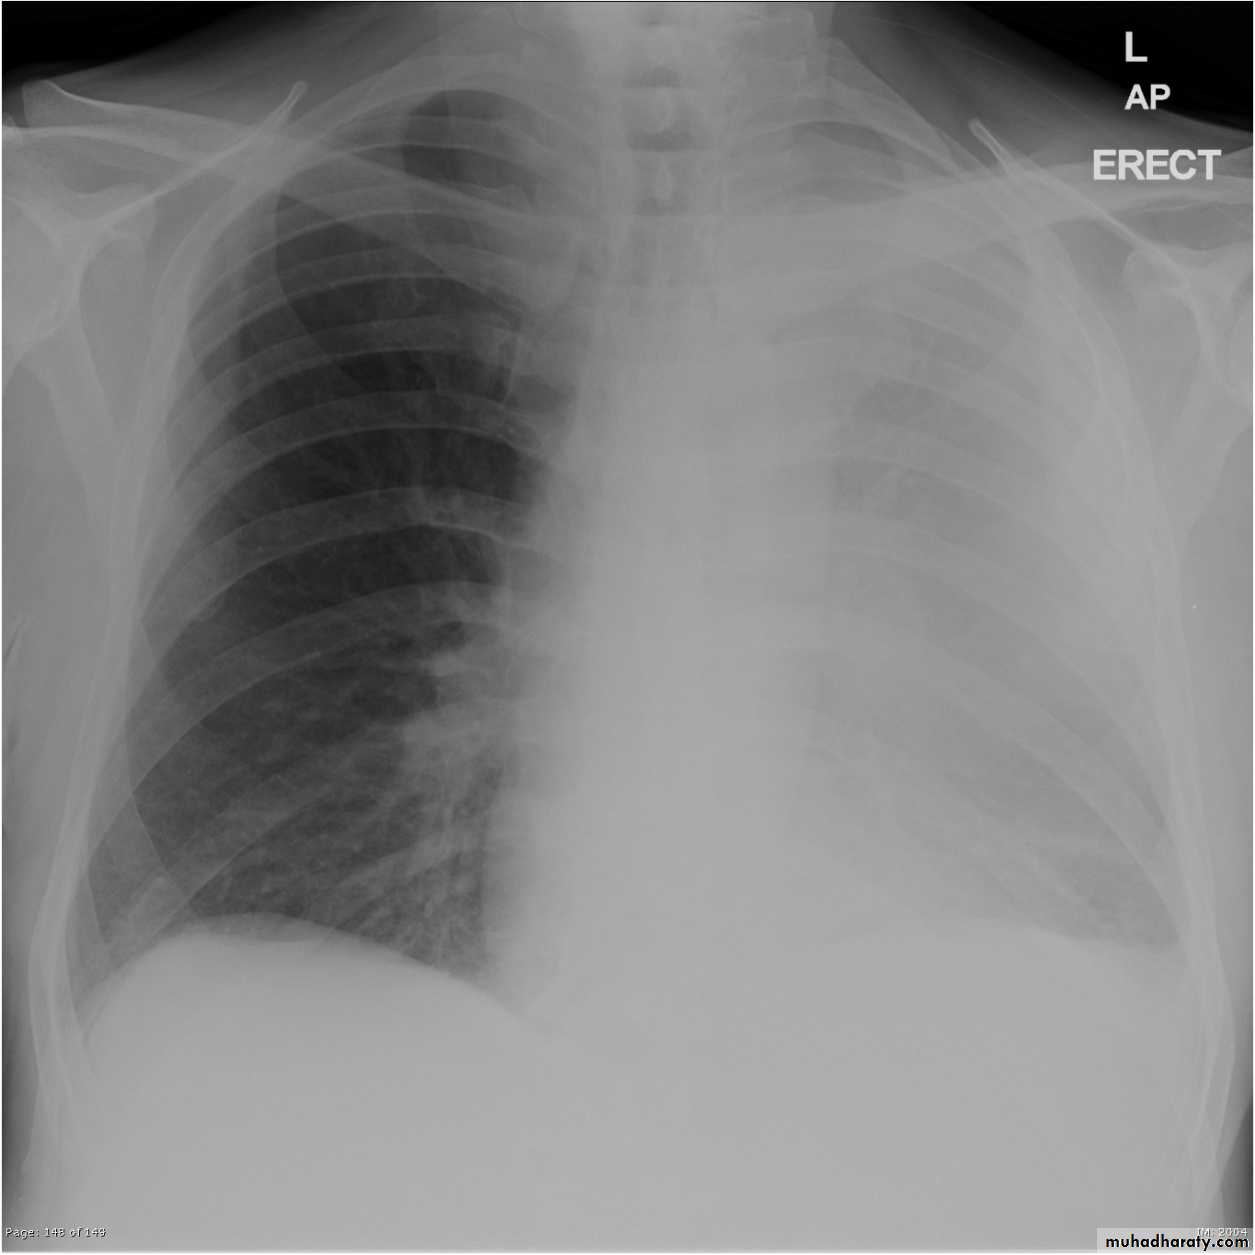

Pleural effusion

Pleural effusion tends to be used as a catch-all term denoting a collection of fluid within the pleural space. This can be further divided into exudates and transudates depending on the biochemical analysis of aspirated pleural fluid. Essentially it represents any pathological process which overwhelms the pleura's ability to reabsorb fluid.Radiographic appearances

Plain radiographChest radiographs are the most commonly used examination to assess for presence of a pleural effusion, however it should be noted that on a routine erect chest x-ray as much as 250-600 ml of fluid is required before it becomes evident 6. A lateral decubitus film is most sensitive, able to identify even a small amount of fluid. At the other extreme, supine films can mask large quantities of fluid.

CXR (erect)

Both PA and AP erect films are insensitive to small amounts of fluid. Features include:

blunting of the costophrenic angle

blunting of the cardiophrenic angle

fluid within the horizontal or oblique fissures

eventually a meniscus will be seen, on frontal films seen laterally and gently sloping medially (note:

with large volume effusions, mediastinal shift occurs away from the effusion (note: if coexistent collapse dominates then mediastinal shift may occur towards the effusion)